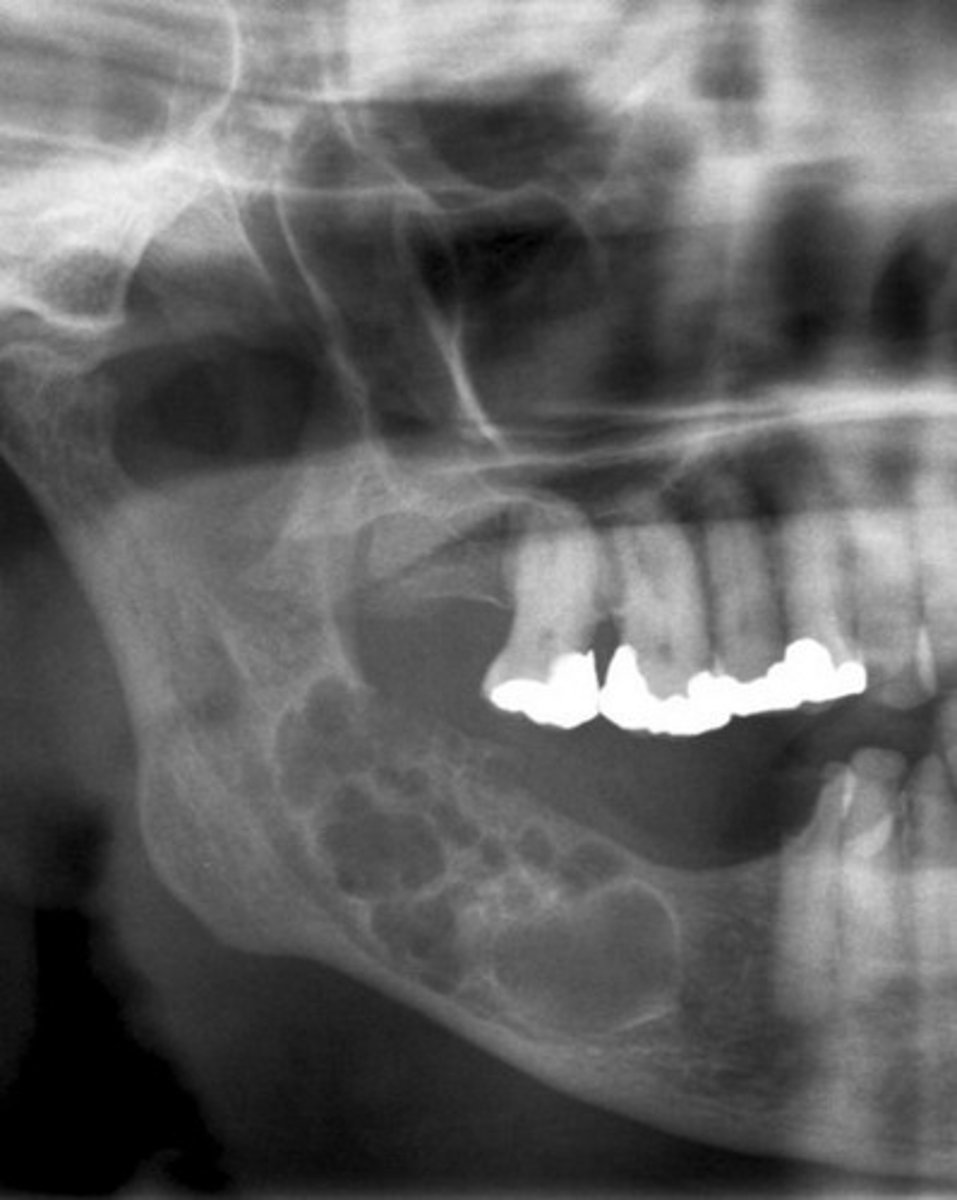

What are the radiographic features of ameloblastomas?

⢠unilocular radiolucency (early lesions)

⢠multilocular radiolucency (honeycomb/soap bubble) (large lesions)

⢠cortical thinning/bone expansion

⢠resorption of adjacent tooth roots + tooth displacement

What is the treatment & prognosis of an ameloblastoma?

⢠treatment: surgical excision - resection for large lesions

⢠prognosis: guarded -- 55-90% recurrence (15% if resection)